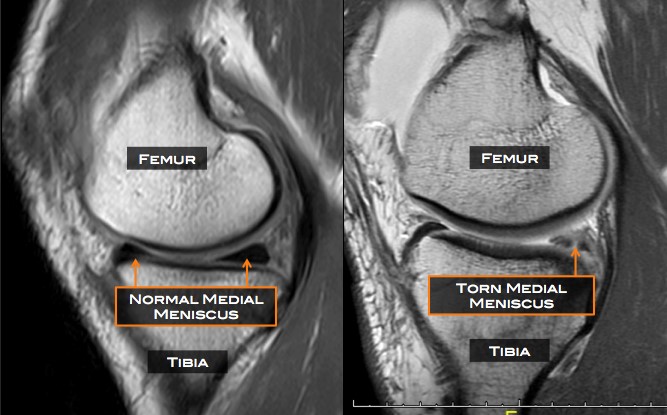

MRI can help diagnostically with soft tissue structures. We have experience reading MRI from class but a clinical setting is very as my reading has weight on the patient case. I was checking for a meniscus tear in the MRI and thankfully I did not see any issues. The radiologist confirmed what I saw. It was a great experience for me looking at the MRI and explaining what I saw to the patient. In my opinion reading MRI is a lot easier than reading X-rays, because the signs are more obvious than some subtle changes on X-ray that could be mistaken for pathology. Sometimes shadows on X-ray can mimic a fracture. As far as I know, there are seldom similar situations for MRIs. Here is a basic comparison of normal and abnormal MRI of a knee.